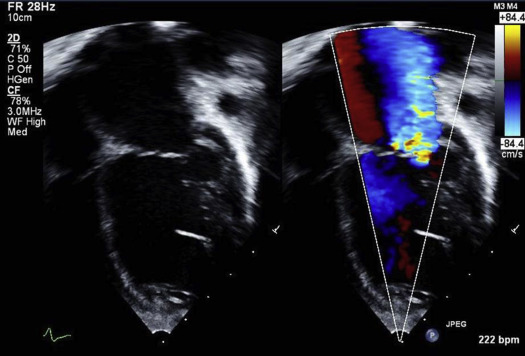

“… Η αδερφή μου νοσηλεύτρια εξουσιοδοτημένη στο νοσοκομείο Baylor στο Dallas, λέει ότι είχε τις τελευταίες 2 εβδομάδες 83 παιδιά από 14 -19 ετών που πάσχουν από μυοκαρδίτιδα λόγω εμβολίου και ότι οι γιατροί ήταν σοκαρισμένοι.2 άλλα νοσοκομεία στο Texas έχουν συνολικά 162 παιδιά με μυοκραδίτιδα.”Σύνολο αμέσως αμέσως 245 παιδιά σε 3 μόνο νοσοκομεία…Kανονική επιδημία εμβολιακής μυοκαρδίτιδας.